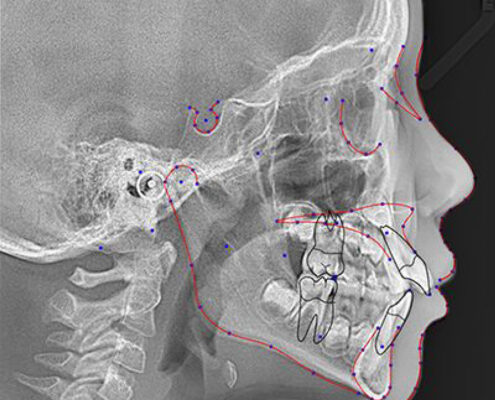

Today’s digital imaging software provides tools that allow for 1:1 measurement of ceph X-rays, which is a concern for many dental professionals migrating from analogue systems. In addition, modern imaging software allows you to create serial superimpositions with cephalometric tracing. The ability to compare and contrast those images can be one of the most effective ways to measure growth, and these images can also help you see how the mouth is responding to treatments such as orthodontics. Plus, advanced treatment simulation modules available in some software packages, allow you to diagnose, plan, and present cases using 2D digital ceph X-rays, improving case acceptance.